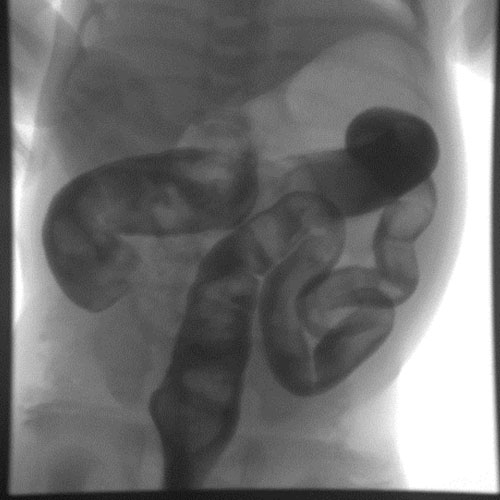

KUB/Supine Abdomen.

An -----French straight catheter was inserted just into the rectum.

An -----French straight catheter was inserted in the mucous fistula.

Under fluoroscopic guidance, the rectum and colon were filled with contrast, and fluoroscopic images were obtained.

The colon was filled through its entire length, confirmed by contrast filling of the appendix and reflux into terminal ileum.

The patient evacuated contrast completely and a post-evacuation overhead radiograph was obtained.

Post-evacuation radiograph showed complete evacuation of the colon.